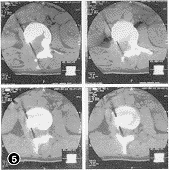

本组23例术后随访最短24个月,最长5年4个月,平均3年8个月。术前脊柱后凸畸形,后凸角18°~45°,平均27.5°,术后为0°~16°,平均6°。17例新鲜骨折病人术后基本矫正(图2~5,插Ⅱ),6例陈旧骨折术后仍有轻度畸形。术后每月摄片1次,骨愈后时间为5~8个月,平均为6个月。术后2例病人出现气胸,均经胸腔闭式引流1周后痊愈。23例病人术前均有不同程度的截瘫,除1例D级为伤后4年,因后凸角较大,故术中做前路植骨,以重建其脊柱中柱、前柱,矫正其后凸成角为目的外,22例均有Frankel一级以上的改善。13例术前有括约肌功能障碍者术后随诊时大部或完全恢复。

图2 X线示L1爆裂骨折 图3 CT扫描示L1前、中、后柱损伤,椎管2/3梗阻 图4 术后随诊X线像示椎体前缘恢复正常高度,椎间隙有骨小梁通过 图5 术后CT扫描示椎管内骨块彻底清除,植骨块与档板位置适中